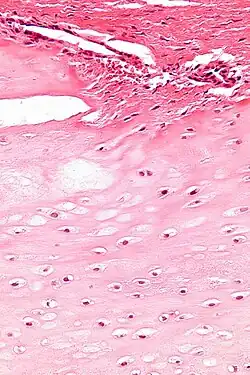

| Micrograph of an enchondroma. H&E stain. |